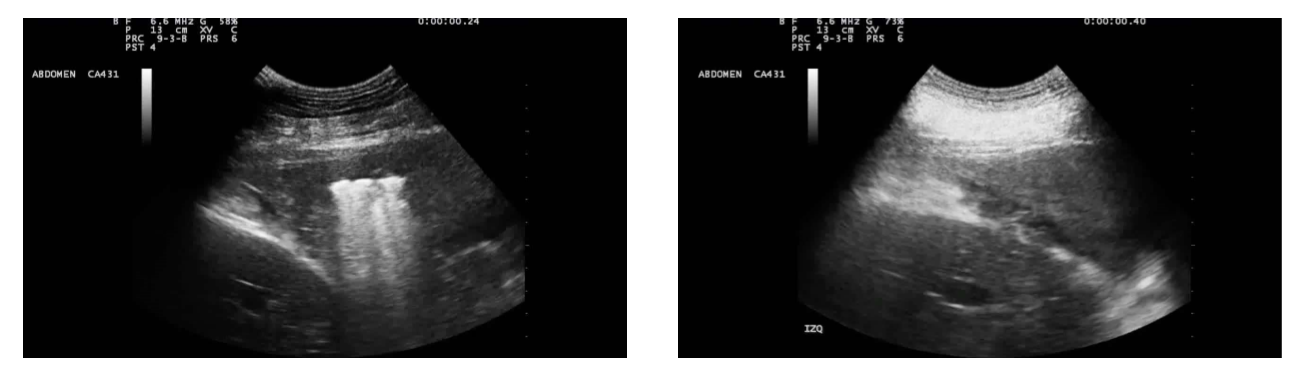

• ultrasound is beneficial for pathology on the periphery of the lung which is affecting or reaching the pleura. The ultrasound may not reach more internal pathology

• On the left, there is a consolidated lung with a small amount of gas. On the right-hand side, there is a consolidated lung without air in it.